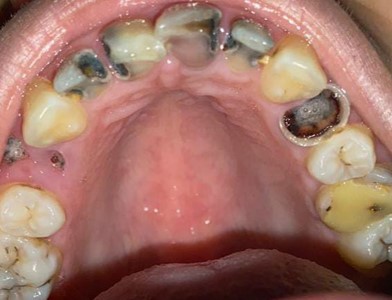

Full E-MAX 4 crowns restoration